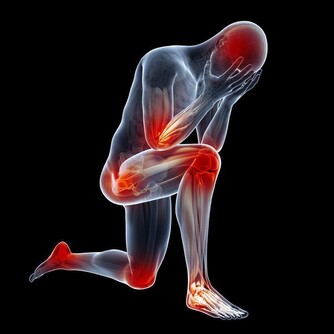

14. 下巴是腎和全身有酸痛的地方;也叫疲勞酸痛區。

15. 整個下巴到耳朵包括耳朵為腎區。